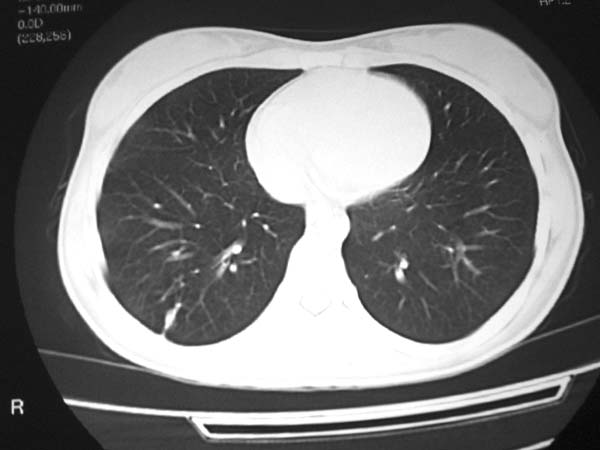

标题: CT13486:F 17Y 咳嗽 咳痰数日请会诊 [打印本页]

标题: CT13486:F 17Y 咳嗽 咳痰数日请会诊

白细胞9600不发烧

右下肺背段病灶,考虑结核与炎症鉴别,请进一步检查.

右下肺外基段病灶,考虑炎症,建议治疗后复查,以排外结核

考虑为:右肺下叶外基底段结核球。

结果;痰中找到结核杆菌

痰涂片已找到结核杆菌  将结果告诉大家